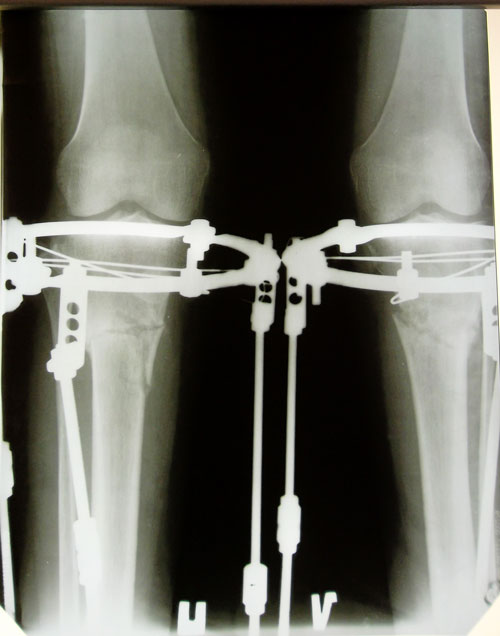

Рентген в 2 месяца после операции.

Здравствуйте, Ирма! Рентген получили, сращение отличное, ось ровнейшая! Ждём на снятие аппаратов через 2 недели!

Дата операции 07.02.2014г.

Дата снятия аппаратов 05.05.2014г.

Срок лечения 87 дней.